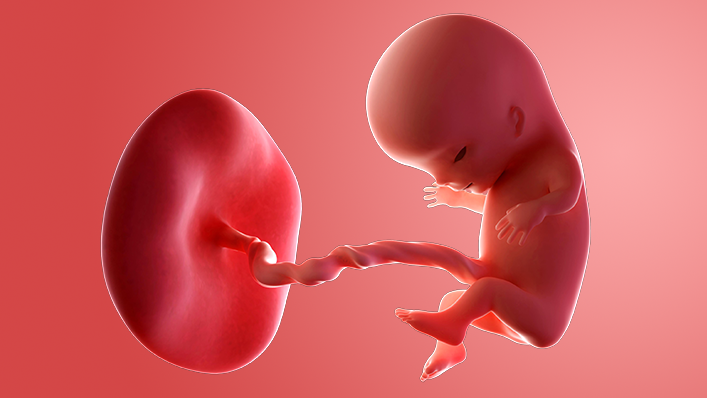

What does my baby look like?

Your baby, or foetus, is now 5.4cm long from head to bottom, which is about the size of a plum.

The internal organs and muscles have grown, and the heartbeat can be picked up on an ultrasound scan. The skeleton is made up from tissue and hardening into bone.

The sex organs have formed, although most scans will not be able to tell your baby's sex until later.